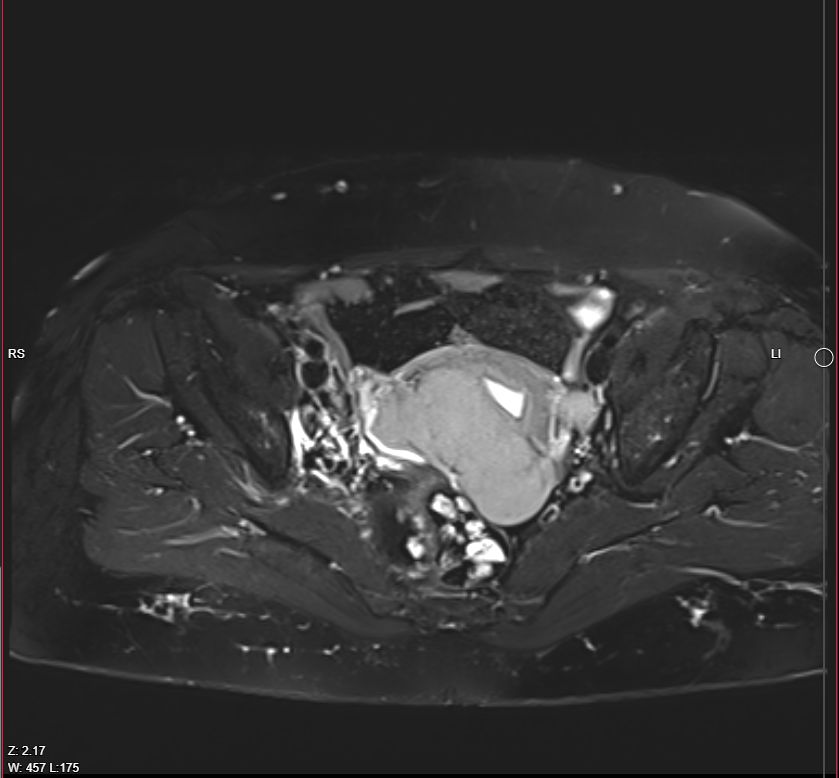

Pelvic MRI With IV Gd:

- Evidence of 7.5 X 4cm mass involves Rt side of uterus reaches endometrium, involves whole thickness of uterus and extends to Rt adnexa, also infiltration of peritoneal reflesion in Rt side of rectouterine pouch, shows marked DWI restriction, picture is suggestive of malignant tumor ?lymphoma ?sarcoma

- Single Lt internal iliac pathological LN, 18mm in short axis diameter, its signal is like uterine mass.

- There is also 26 X 22mm lesion in Rt internal iliac region, but heterogeneous signal ?pathological LN with necrosis

- Endometrial thickness is 8 mm, no obvious focal mass.

- Mild pelvic free fluid.

- Normal both ovaries in size, no mass.

- Normal UB in wall thickness.

- No obvious rectal pathology.

- No pelvic bone lesion.